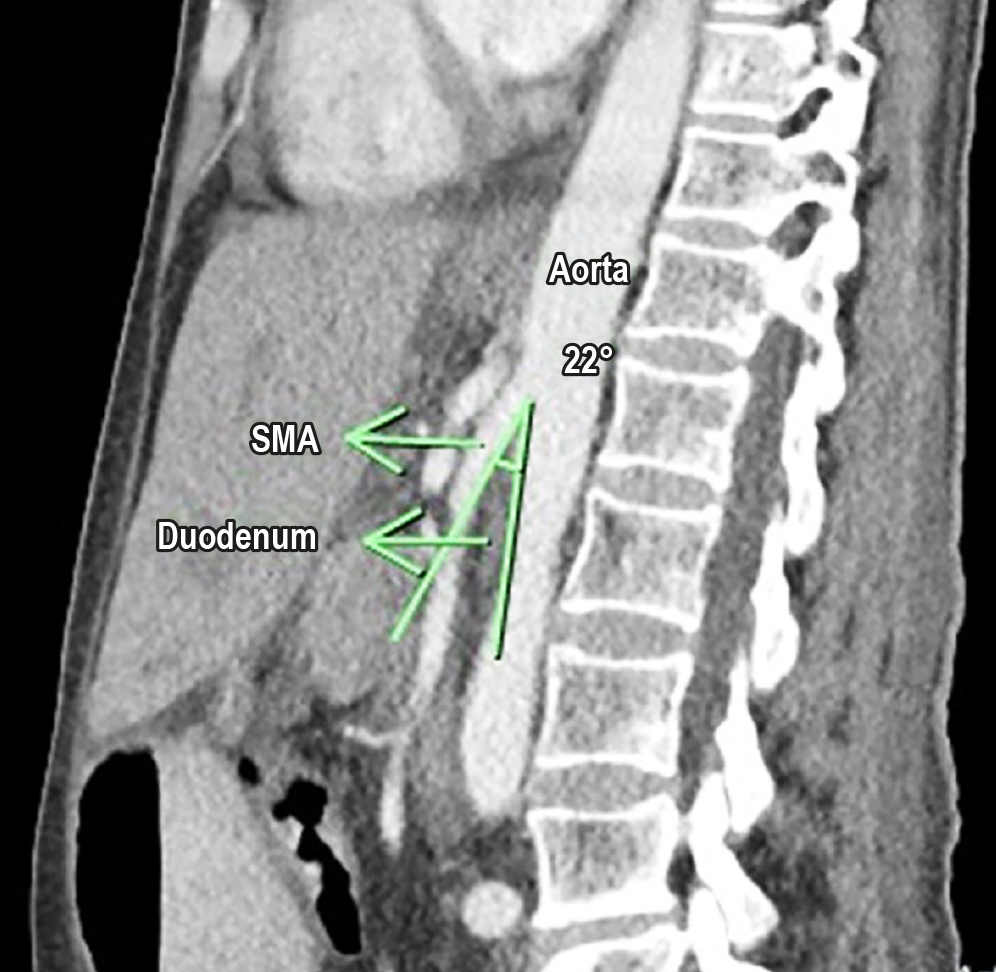

Introducción: el síndrome de la arteria mesentérica superior (SAM) es una condición rara de obstrucción intestinal de la tercera porción con un origen vascular. Es subdiagnosticada y tiene múltiples distractores, lo que implica un retraso en su diagnóstico, pero conlleva una alta tasa de morbimortalidad. Su base fisiopatológica es la pérdida de peso, y es más común en mujeres jóvenes, en las que el manejo médico o quirúrgico mínimamente invasivo es el tratamiento en la actualidad.

Presentación del caso: es una mujer de 61 años con síntomas insidiosos de seis meses de evolución de dolor abdominal y múltiples episodios eméticos asociados a una pérdida marcada de peso con diagnóstico tomográfico de SAM, condicionado por la recaída tumoral de cáncer de mama. Se indicó manejo conservador, pero hubo desenlace fatal por complicaciones infecciosas.

Conclusiones: el SAM es raro y su diagnóstico es difícil. Múltiples causas asociadas llevan a pérdida de peso, que es la base de su fisiopatología. La tomografía y la resonancia son las imágenes de elección y actualmente el manejo conservador es la primera línea con alta tasa de recurrencia, y escoger una opción quirúrgica debe ser susceptible de una alta morbilidad derivada del proceso quirúrgico.